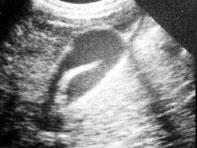

选项 A、阑尾炎的压痛、反跳痛主要在右下腹 B、胆道蛔虫病常出现腹膜刺激征 C、胃、十二指肠溃疡穿孔的压痛、反跳痛以上腹部最明显 D、胰腺炎病人血尿淀粉酶增高 E、胆总管结石的腹痛常伴发热和黄疸